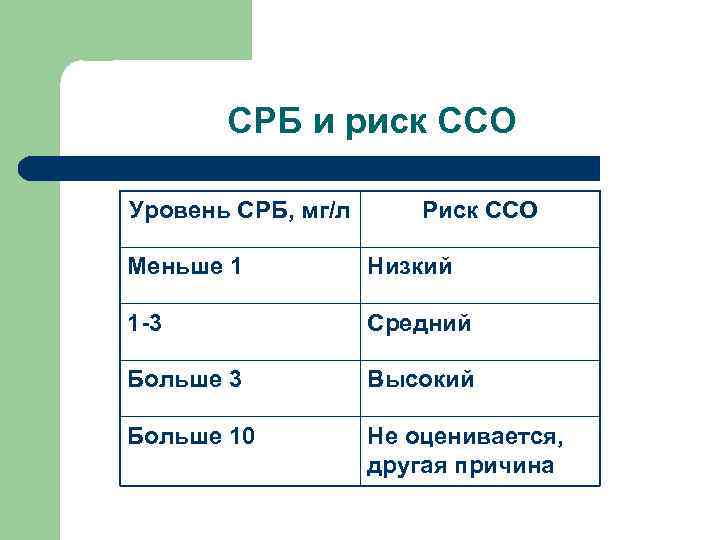

СРБ и риск ССО Уровень СРБ, мг/л Риск ССО Меньше 1 Низкий 1 -3 Средний Больше 3 Высокий Больше 10 Не оценивается, другая причина